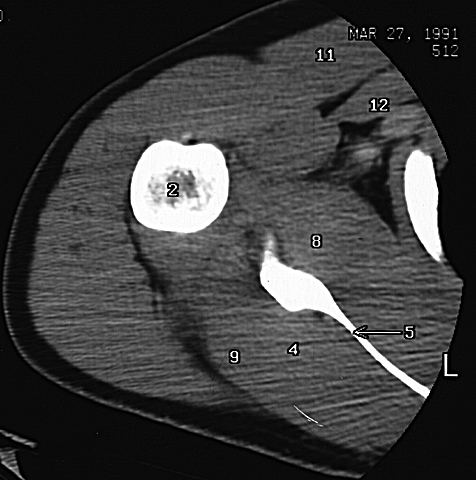

2. Humerus

4. Infraspinatus m.

5. Scapula

8. Subscapularis m.

9. Teres minor m.

11. Pectoralis major m.

12. Pectoralis minor m.